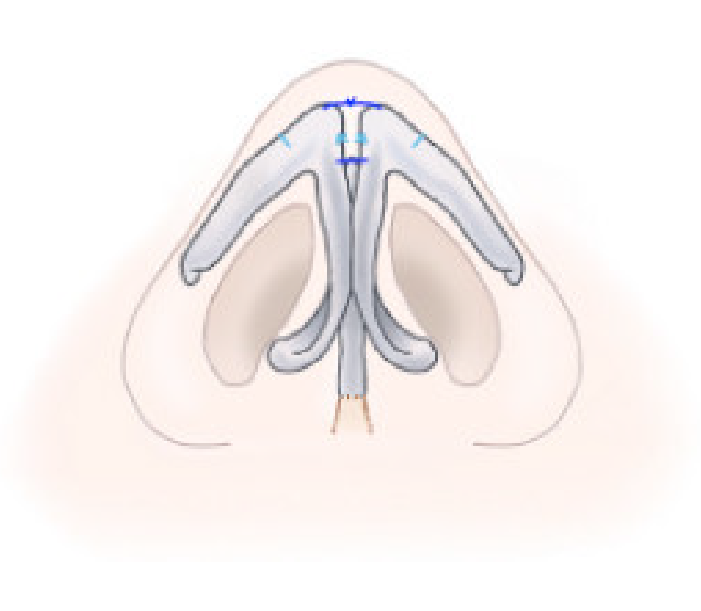

上図の赤い点線の三日月形の部分を皮膚のみを切除し、軟部組織を残します(フラップ)。

ピンクの部分(フラップ)を、赤い点線のところにトンネルを作成し、左右の軟部組織(フラップ)を引き込みます。

このように寄せ合うことで、面と面で寄せられ、より自然な形態となります。傷はとても目立ちにくく、鼻の存在感が控え目になります。

第58回 日本形成外科学会総会・学術集会で報告した方法

鼻翼縮小術は鼻孔底で部分切除する方法が、鼻の幅を狭くすることができるため広く行われています。この方法の利点は瘢痕を隠しながら鼻の幅を狭くする点であるが、時々特有のnotchingや角のある鼻孔形態を呈することがあります。

プリモ麻布十番クリニックではnotchingを来しにくい自然な鼻孔形態となる鼻翼縮小術を考案し実践しています。

新しい鼻翼縮小術のデザインは、鼻孔縁のコーナー部分を温存し、nostril sill部分の切除を鼻翼の辺縁に合わせるようにデザインします(内側法)。切除幅は希望の縮小程度により変化させます。

Nostril sill切除範囲内に切除幅の長さの三角弁をデザインします。

footplate方向へ同じ長さだけ鼻腔底を切除するデザインを作成します。

15番メスで皮膚切開を行い、デザインした組織を切除します。

cinching sutureを用い、埋没縫合は4-0 PDS、皮膚縫合を7-0 Nylonでおこないます。

鼻翼の張り出しの大きい症例はnostril sill部分切除に加え鼻翼外側方向へ切除を追加します(外側法)。

鼻翼内側の切除幅、鼻翼外側での切除幅をそれぞれ希望とご状態に応じて決定します。

内側法の切除範囲内に三角弁をデザインします。この三角弁の部分は切除せず残します。

鼻柱方向に同じ長さの三角形の切除範囲をデザインします。

内側から外側までデザイン通りに鼻翼の皮膚切除を行います。

Cinching sutureを用いたうえ、埋没縫合を6-0吸収糸で行い、皮膚縫合を7-0 Nylon糸で行います。